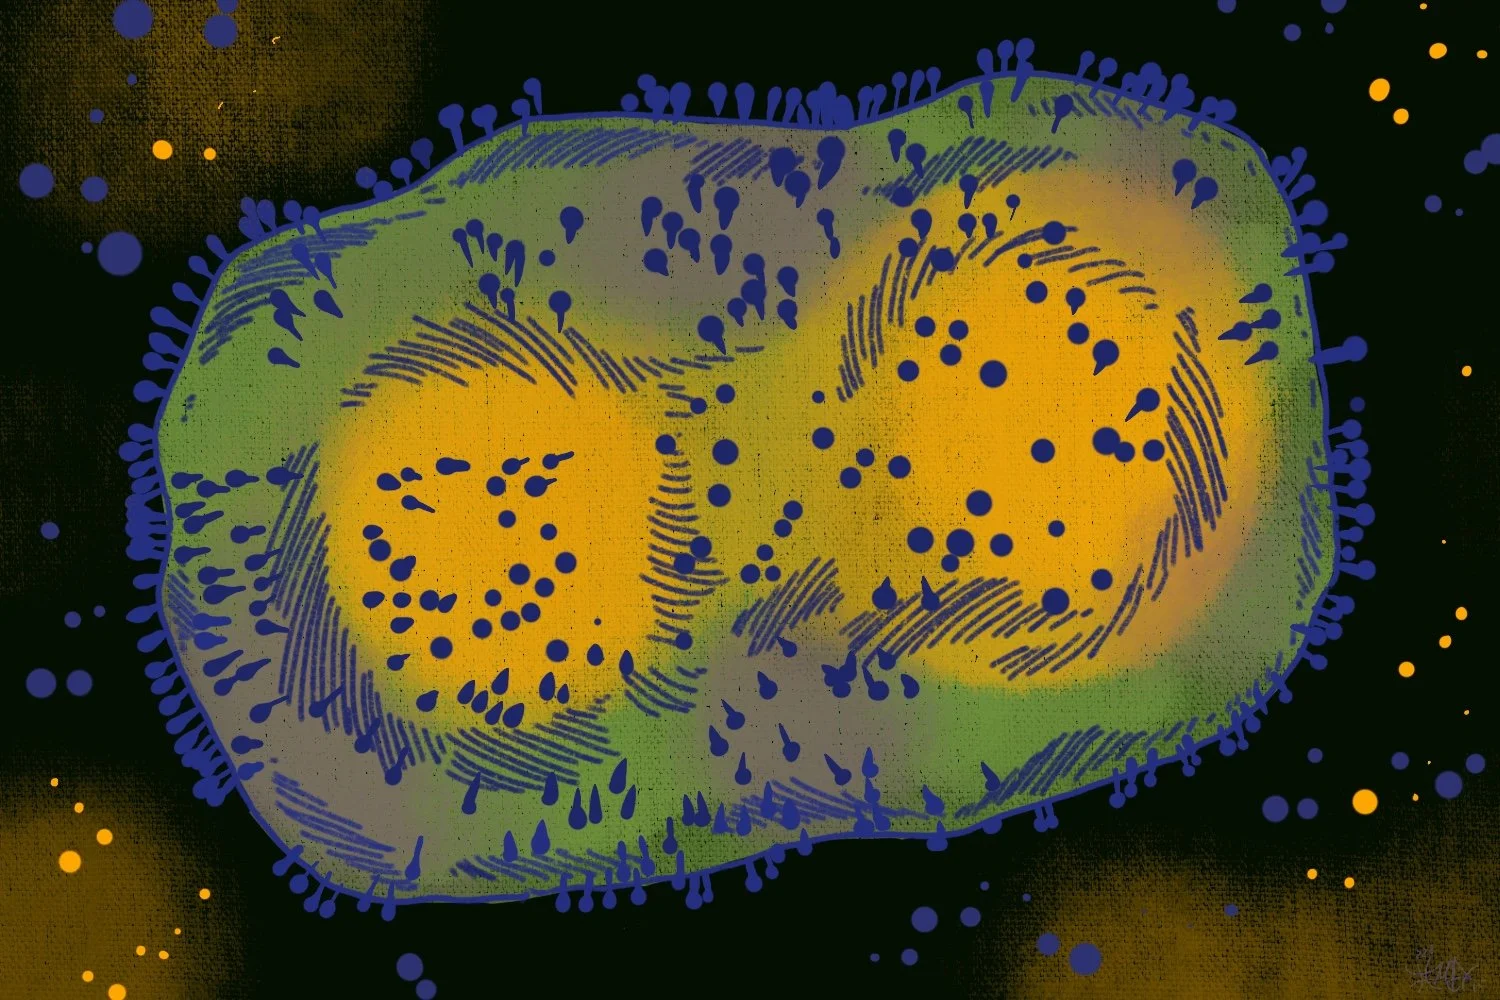

No immediate University response plans in place for monkeypox